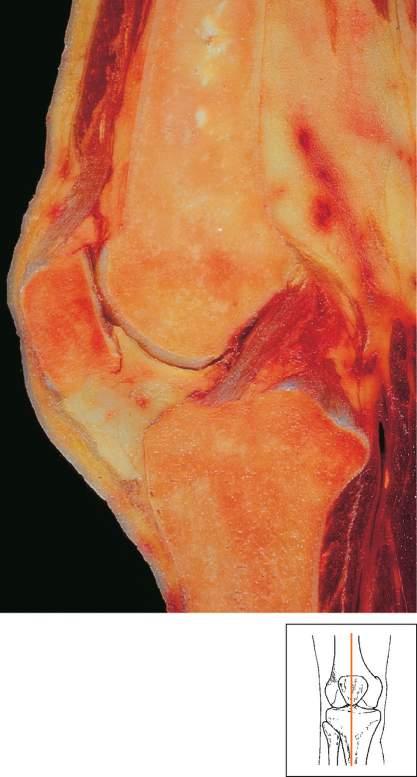

Theplainradiographsoftherightkneerevealedsignificantjointspacenarrowingandosteophyteformationconsistentwithsevereosteoarthritis(Fig.1.1).

Fig.1.1 Osteoarthritisoftheknee.AnteroposteriorstandingkneeX-raywithjointspaceloss,especiallyinthemedialcompartmentandosteophytesbilaterally.(FromVincentTL,WattFE.Osteoarthritis. Medicine.2018:46[3]:187 195[Fig.3C].)